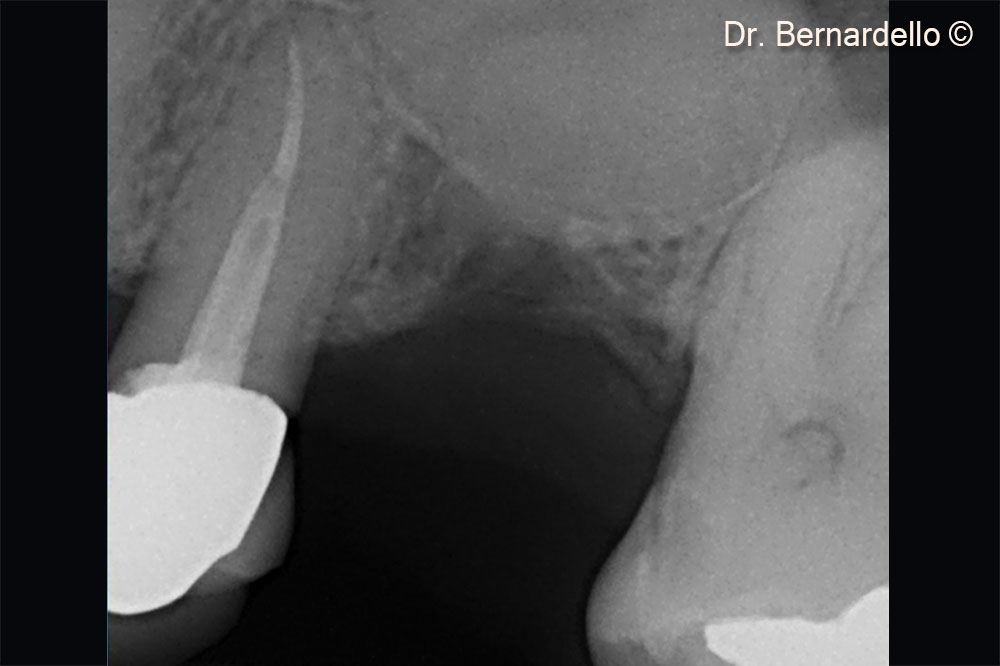

Initial situation

Based on sinus width, a female patient (55 years old) is considered eligible for a transcrestal sinus floor elevation

Based on the sinus width, the patient is considered eligible for a transcrestal sinus floor elevation